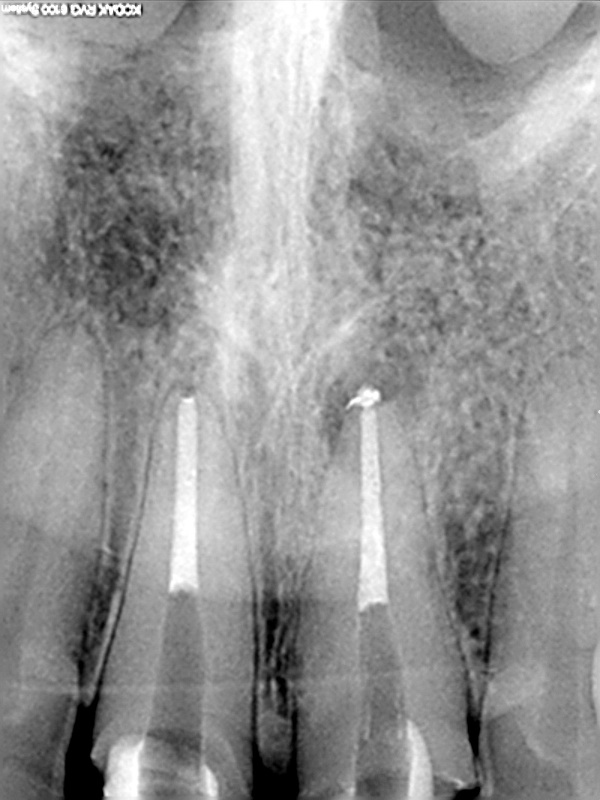

und wieder ein Recall

WF Kontrolle